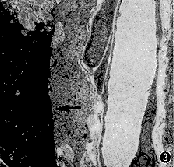

3.透射电镜观察:黄斑下NVM主要由新生毛细血管组成。管壁由血管内皮细胞和周细胞构成,管壁外可见不完整的类似基底膜的成分,管腔内除血浆成分外,偶见白细胞(图1)。在病理切片中可见尚未形成血管腔的内皮细胞和周细胞(图2)。此外,也偶见RPE细胞(图 3)。血管间质充满丝状的血浆沉积物(图4)。

图1 透射电镜对NVM的观察显示,其主要成分为新生血管(箭头)。管壁由血管内皮细胞和周细胞构成,管壁外可见不完整的类似基底膜成分。管腔内除血浆成分外还可见白细胞 ×2 000